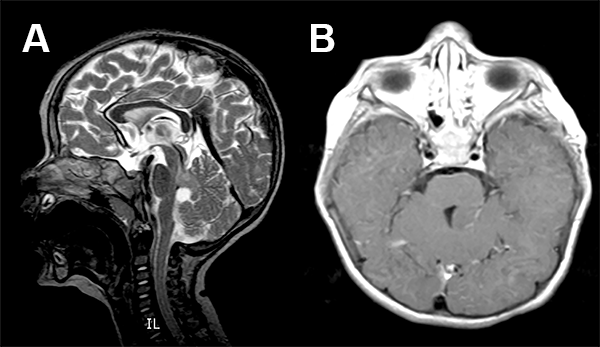

La RMN mostró una lesión tumoral en el hemisferio cerebelos derecho en intimo contacto con los pedúnculos cerebelos medio y superior derecho (fig. 6).

Figura 6: Caso 3. Imágenes prequirúrgicas.

Paciente de 4 años de edad sin antecedentes perinatológicos de importancia que a los 3 años de edad comienza con movimientos clónicos de comisura labial a derecha que fueron asumidos como normales. Ocho meses después del inicio de los movimientos clónicas de la comisura labial, la niña presenta fijeza de la mirada con posterior desviación de la comisura labial a derecha y posteriores movimientos tónicos clónicos generalizados que se repitieron varias veces (fig. 7).

Figura 7: Caso 4: Imágenes preoperatorias